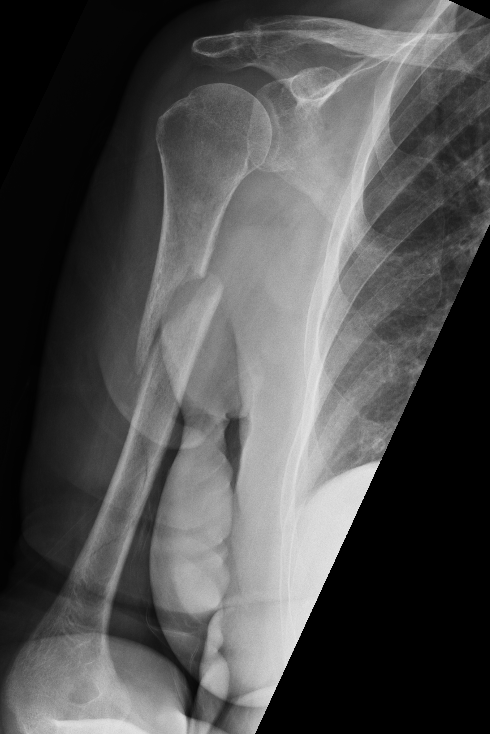

Prox humerus 1Prox humerus 2Prox humerus ORIFProximal humerus ORIF

Proximal third humerus ORIF of nonunion